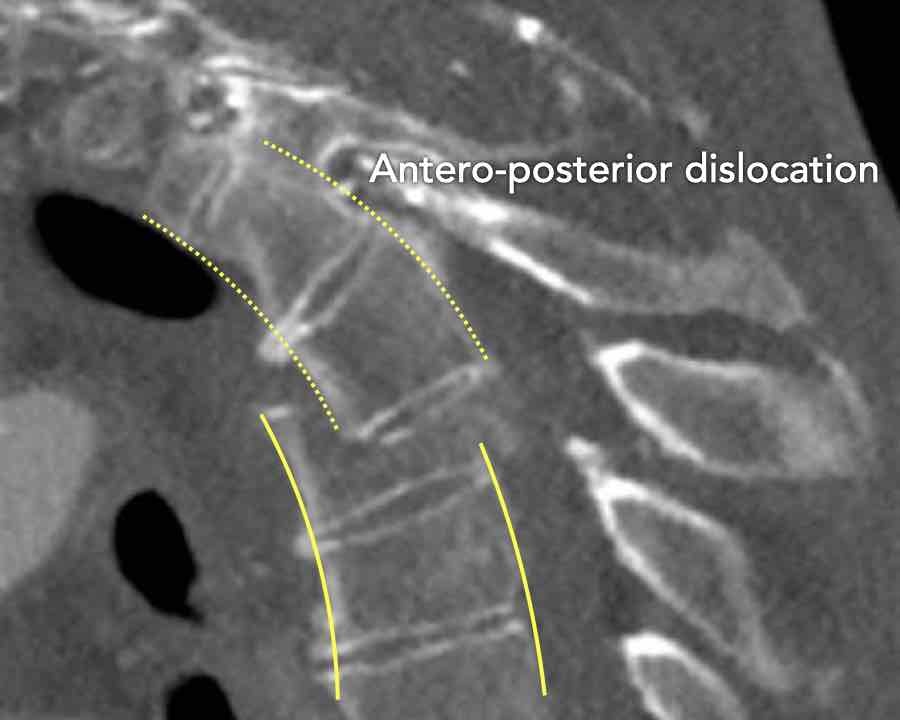

Scroll through the images

Findings:

- Perched facet joints (yellow curved arrows), so think of C injury.

- Posterior displacement of the vertebral bodies in the midline.

- Secondary A4 injury of the vertebral body.

Conclusion

Type C + A4 injury